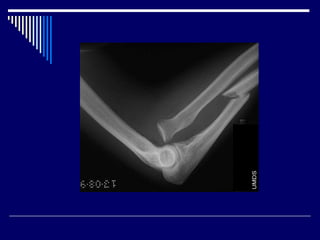

7.Supracondylar fracture

90% are seen in children younger than 10 years

commonly seen in boys

Lateral and AP radiographs are usually sufficient

• #35 Typically supracondylar fractures occur as a result of a fall on a hyper-extended elbow.  posterior displacement of the distal component.  extra-articular fracture line indirect signs is essential:  anterior fat pad sign (sail sign) - the anterior fat pad is elevated by a joint effusion and appears as a lucent triangle on lateral projection posterior fat pad sign anterior humeral line should intersect the middle third of the capitellum in most children  although in children under 4, the anterior humeral line may pass through the anterior third without injury

• #37 In the setting of a painful elbow following a fall, if this line does not intersect the green area, but rather the red area then a supracondylar fracture should be suspected.

• #38 AP and lateral radiographs of the elbow demonstrate a lucency across the distal humerus consistent with a supracondylar fracture. A line drawn along the anterior border of the humerus does not intersect the middle third of the capitellum, indicating that the fracture is somewhat posteriorly angulated.

• #55 A joint effusion with sail sign and an anterior cortical supracondylar breach is present.  Anterior humeral line continues to intersect the mid point of the capitellum.  Completely displaced (posterormedial displacement) supracondylar fracture.

• #56 There is an acute distal one-third radial diaphyseal fracture with dorsal lateral displacement and volar angulation of the distal fragment. There is also distal radioulnar dislocation with dorsal displacement of the ulna. Findings are keeping with type 1 Galeazzi fracture-dislocation. Remaining osseous structures are intact. No destructive bony lesions.